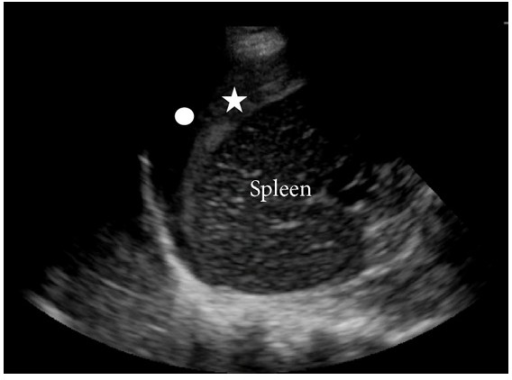

LUQ

The spleen is much smaller than the liver and thus the RUQ acoustic window is small: this view is technically more difficult to obtain. Collections form between the spleen and diaphragm. The spenorenal interface is preserved by the splenorenal ligament.

The star indicates clotted blood adherent to the spleen. Jackson H, et al. - CC BY 3.0, Link